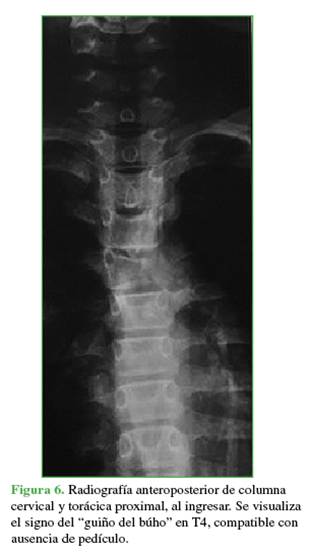

En la radiografía anteroposterior de ingreso, se identificó la ausencia de una imagen pedicular en la vértebra afectada, signo conocido como “guiño del búho” (Figura 6).12

La zona afectada era 3-6, niveles III y IV de la clasificación de Weinstein-Boriani-Biagini.11 En los estudios complementarios, se observaron múltiples quistes tabicados con niveles líquido-líquido, por lo que se descartó un quiste óseo simple, de características expansivas y compresivas, ante este patrón se descartó la posibilidad de un hemangioma vertebral (Figuras 7 y 8). Este caso también se interpretó como una lesión secundaria a un QOA grado 3 de Enneking.13